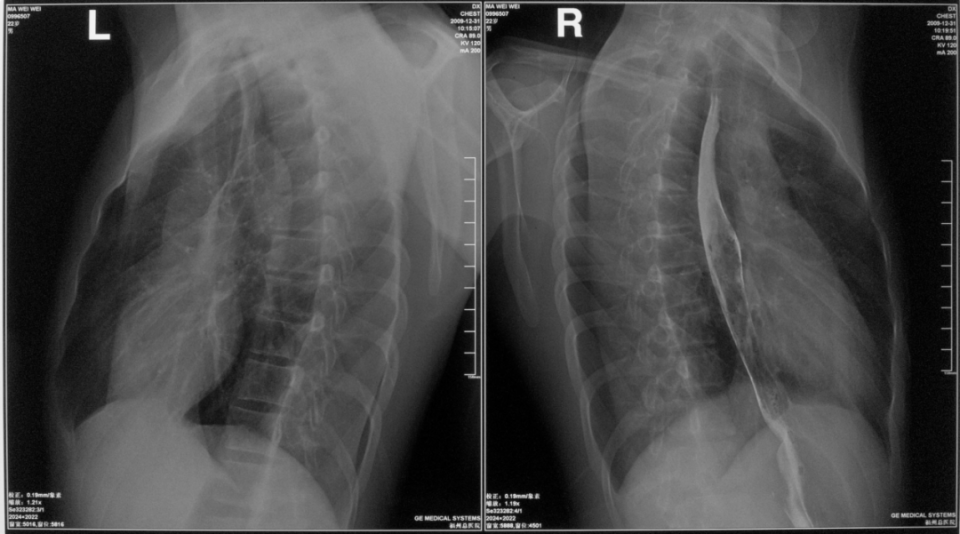

胸部正侧位片

图片

胸部右侧位片

胸部双斜位片